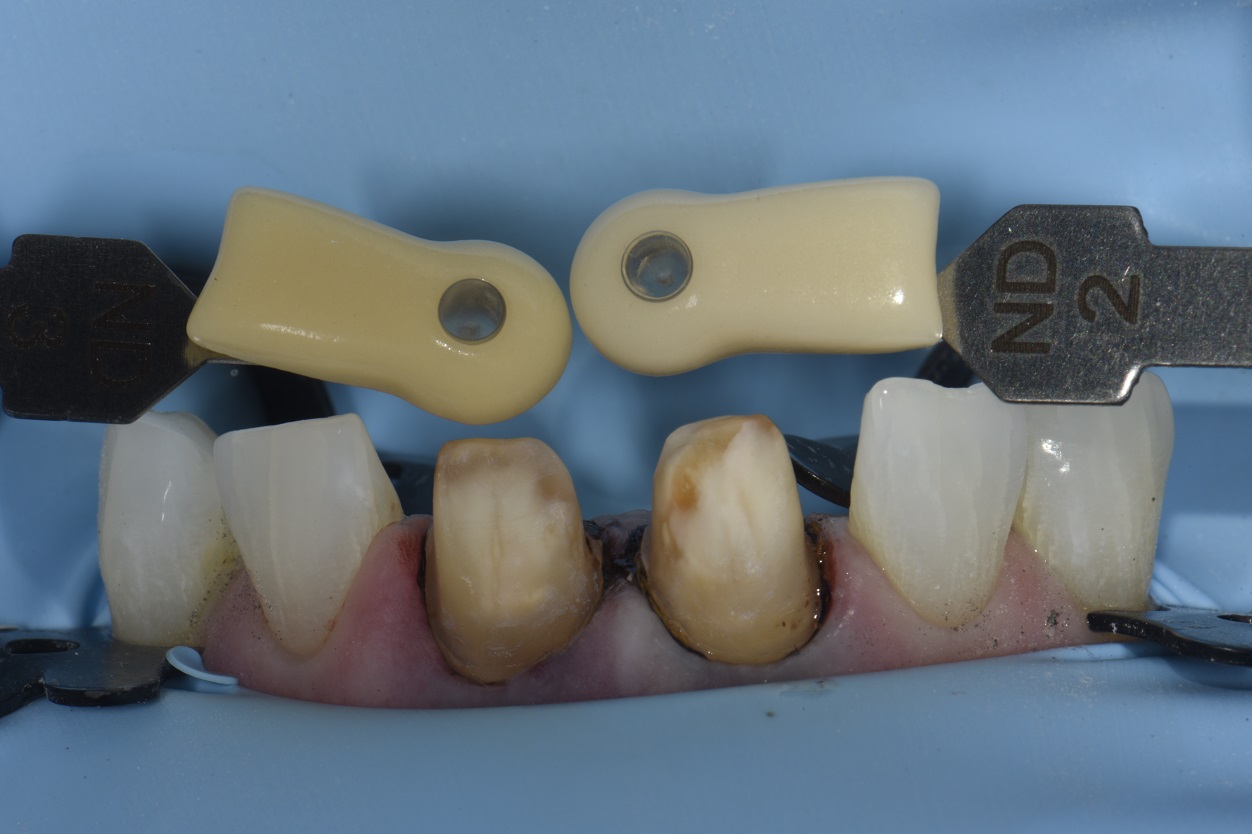

From www.clarencetam.co.nz

Workflow to Replace Two Old Crowns How Do They Remove An Old Crown The dentist will first numb the gums to reduce discomfort. An adhesive may also be used on the permanent crowns to weaken the cement. At times, the dentist may use the old crown if it is not severely damaged. Depending on a multitude of factors, that number will vary. If you suspect that your old dental crown needs to be. How Do They Remove An Old Crown.